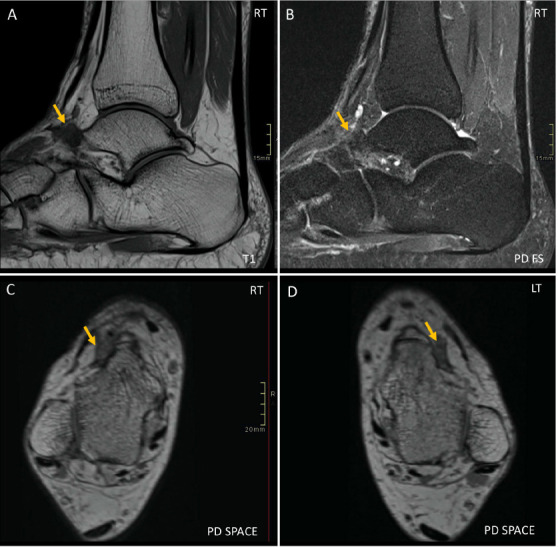

跗骨前隧道综合征是一种少见的压迫性神经病变,累及前踝关节下伸肌视网膜带下腓深神经,常在医学图像上被忽视,导致诊断和治疗延迟。我们提出的情况下,一个52岁的男性,一个狂热的跑步者,谁表现出烧灼感和刺痛感在双脚背部区域。电生理检查提示双侧腓深神经病变。随后的磁共振成像显示双侧病灶区信号改变,与瘢痕一致,包围腓深神经在跗骨前隧道。这些区域被下伸肌视网膜的深椎板压痕,提示压迫。这些发现与跗骨前隧道综合征一致。这是一个独特的病例双侧腓深神经卡压加重重复性微创伤,最终在跗骨前隧道综合征。值得注意的是,这个病例代表了文献中MRI在诊断中发挥关键作用的第一个实例。

Anterior tarsal tunnel syndrome, an infrequent entrapment neuropathy involving the deep peroneal nerve beneath the inferior extensor retinaculum in the anterior ankle, is often overlooked on medical images, leading to delayed diagnosis and treatment. We present the case of a 52-year-old male, an avid runner, who exhibited a sensation of burning and tingling in the dorsal region of both feet. Electrophysiologic studies suggested bilateral deep peroneal neuropathy. Subsequent magnetic resonance imaging revealed bilateral focal regions of signal alteration, consistent with scarring, encasing the deep peroneal nerves at the anterior tarsal tunnel. These regions were indented by the deep laminae of the inferior extensor retinacula, suggesting compression. The constellation of findings was consistent with anterior tarsal tunnel syndrome. This is a unique case of bilateral deep peroneal nerve entrapment exacerbated by repetitive microtrauma, culminating in anterior tarsal tunnel syndrome. Notably, this case represents the first instance in literature where MRI played a pivotal role in diagnosis.